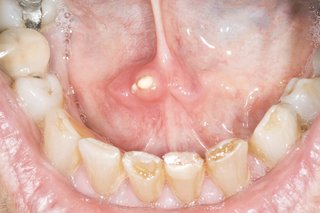

The inside of a person's mouth showing their lower teeth and bottom lip. There is something large and white (a salivary gland stone) under their tongue.

Salivary gland stones are white and hard.